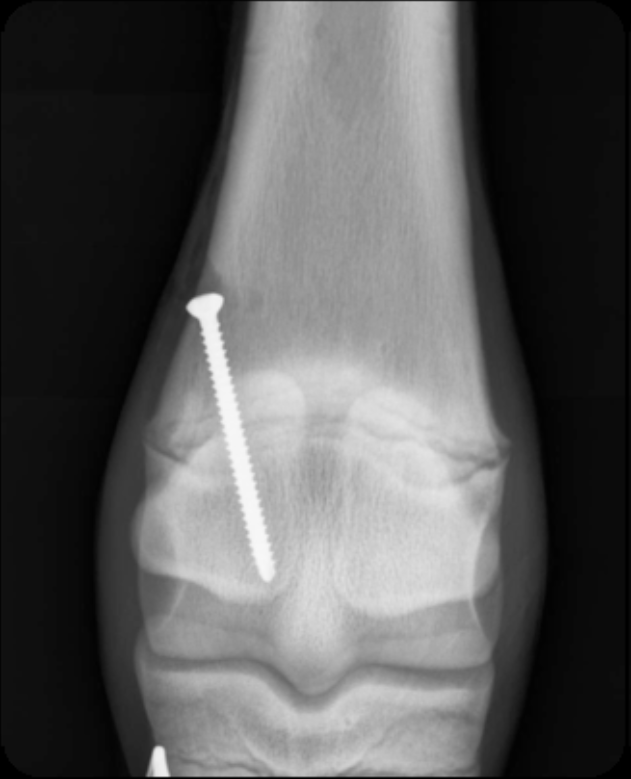

use of transphyseal screw

most common technique

single cortical screw placed THROUGH physis

performed on distal radius, tibia, distal MC/Mt 3